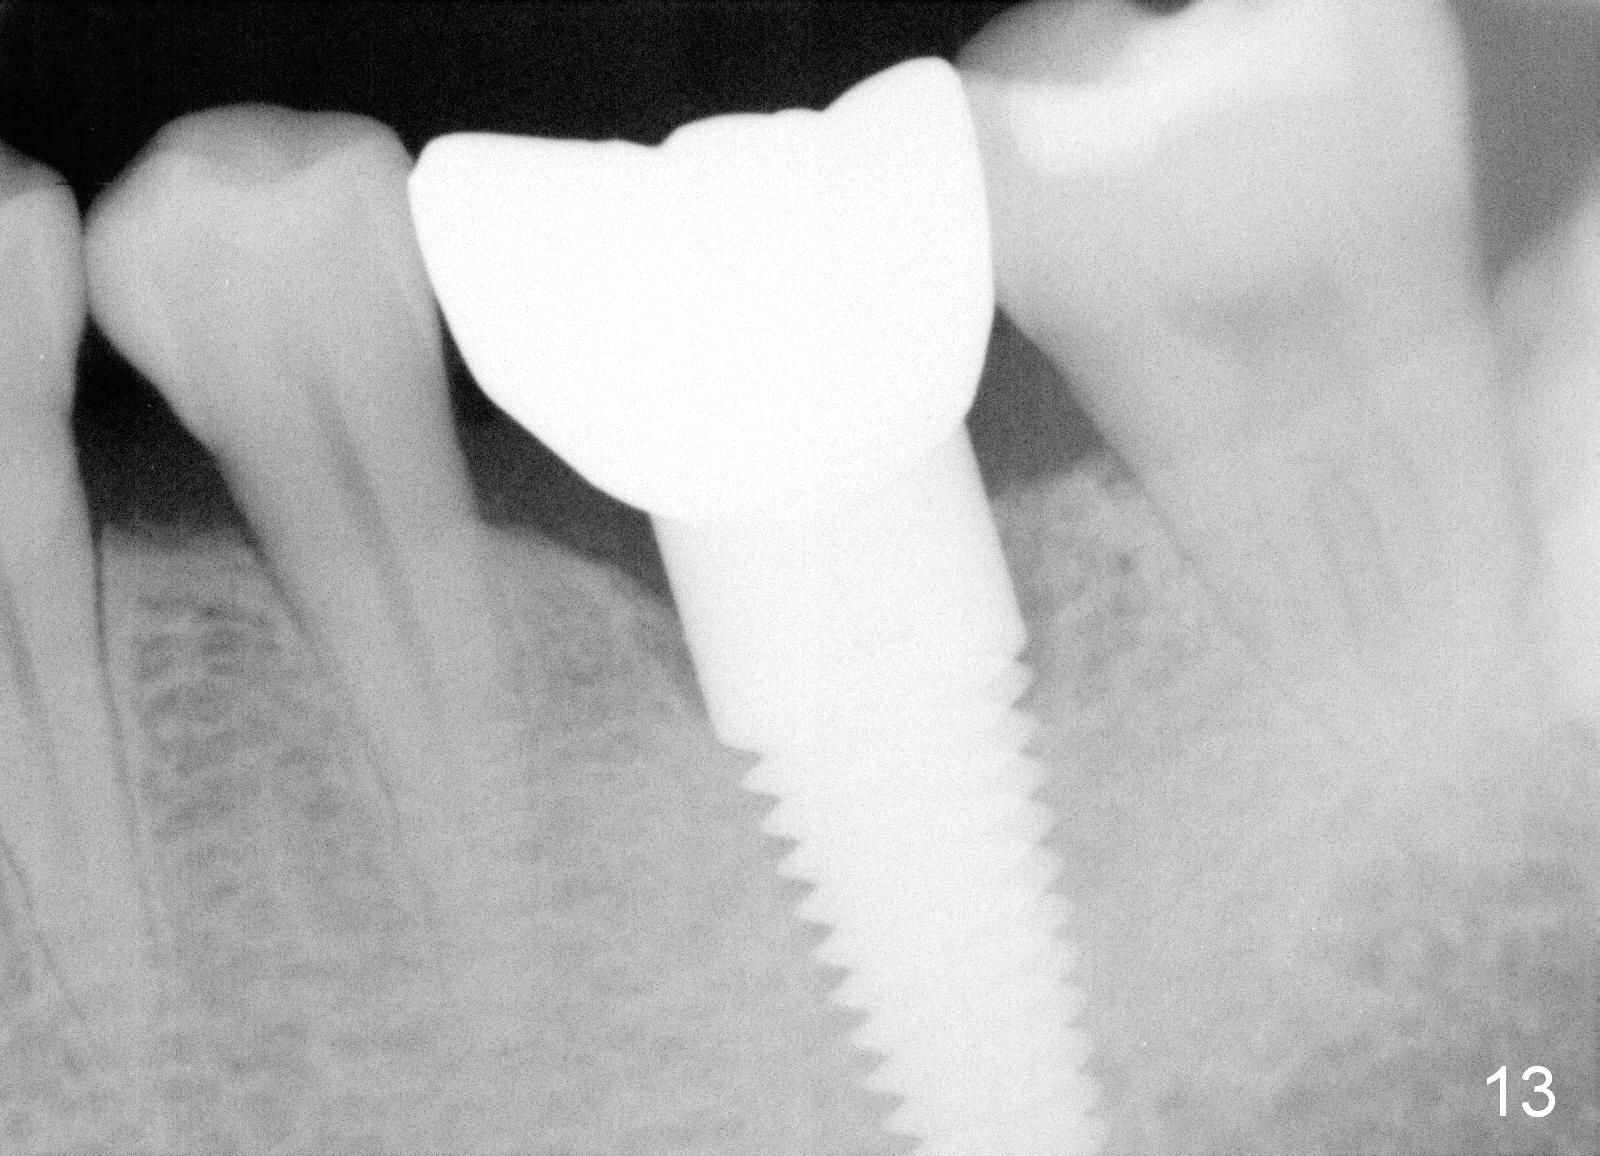

Two and a half months post cementation, the buccal metal show is much less and confined to the midbuccal portion. It appears that the papillae increase their mesiodistal dimension (data not shown). Bone appears to remain stable over the implant surface 2.5 and 9 months post cementation (Fig.12 >,13). The papillae around the implant crown remain normal 11 months post cementation (Fig.14 *). No bone loss is noticed 26 (Fig.15) or 38 (Fig.16) months post cementation. There is no bone loss around the 7x17 mm tissue-level implant 6 years 8 months post cementation (Fig.17).